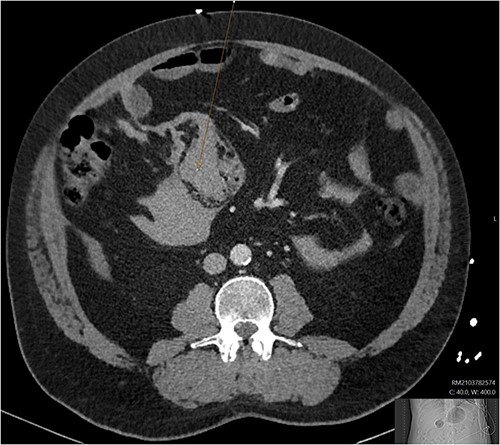

A CT abdomen-pelvis (CT-AP) revealed an acute haematoma inferolateral to the third part of the duodenum and another at the root of the mesentery. High density fluid related to the mesenteric bleed was also seen extending from the right para-colic gutter into the pelvis and in the peri-hepatic region. The patient was admitted under general surgery, stabilized with intra-venous fluid resuscitation, co-amoxiclav and metronidazole and cross matched for four units of blood. A CT-angiogram demonstrated acute haemorrhage throughout the abdomen with a 104 x 62 mm haematoma arising centrally at the level of L2 within the mesenteric fat (Fig. 1). The haematoma did not appear to originate from any specific mesenteric vessels but was related to some mid and distal jejunal loops. The angiogram also showed discontinuity when tracing the proximal and mid jejunal loops inferiorly, extensive haemorrhagic peritoneal fluid around the liver extending inferiorly (Fig. 2) and a small amount of peri-splenic haemorrhagic fluid. Curved reformatting of the angiogram revealed no abnormalities within the superior mesenteric artery (Fig. 3).

CT angiogram showing a peri-hepatic haematoma. Figure 2 is an axial section taken from the patient’s initial CT angiogram of the abdomen and pelvis. A large crescent shaped peri-hepatic haematoma is highlighted by the arrow displayed.